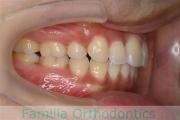

No.22V-299

- 上顎前突

- 叢生

- 30歳

- 女性

- 上:

- 44

- 下:

- 主な使用装置:

- FEA 022

- 治療にかかった費用:

- 90万円

上の出っ歯、口が閉じにくい、下の前歯のガタガタを治したいということで来院されました。上顎から左右小臼歯を、下の前歯は凹凸が非常に強いので、こちらから一本抜歯を行いました。2年強、30回程度の通院が必要でした。

成人になってからの叢生(でこぼこ、凹凸、ガタガタ)は、保定をしっかりしないと後戻りをしてしまうリスクが高いです。